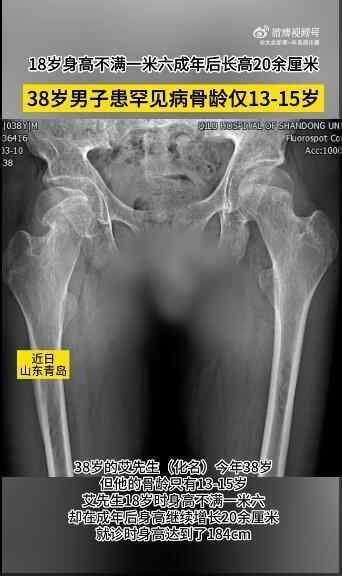

山东青岛的艾先生(化名)今年38岁,但他的骨龄只有13-15岁。

据了解,艾先生18岁时身高不满一米六,却在成年后身高继续增长20余厘米,身高达到了184cm。到医院就诊发现患有一种极为罕见且复杂的病症组合:垂体柄阻断综合征合并股骨头骨骺滑脱。

垂体柄阻断综合征是一种由于垂体发育异常或形态异常所致的罕见病症,常导致激素分泌与调节异常,主要表现为生长发育迟缓、性腺发育不良、甲状腺功能减退以及肾上腺皮质功能减退等症状。而股骨头骨骺滑脱这一多见于青少年的病症,则进一步加剧了他的病情,使他不得不面对疼痛和活动受限的困扰。

目前,艾先生接受了右股骨头骨骺滑脱闭合空心钉内固定术,术后疼痛症状得到了明显的缓解,活动能力也有所恢复,预后良好。